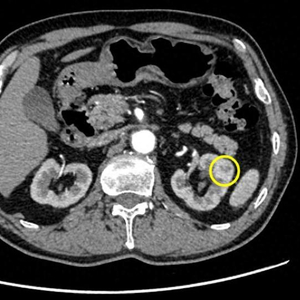

72岁的陈老伯在一次体检中发现在其胃窦体交界处有一处周围隆起、中央凹陷性的病灶,活检病理提示倾向认为是低分化腺癌。陈老伯随后来到仁济医院胃肠外科表示希望进行根治性手术治疗。但在入院检查中,医院意外发现陈老伯的右肾中部有个1公分结节,增强CT高度怀疑肾癌。